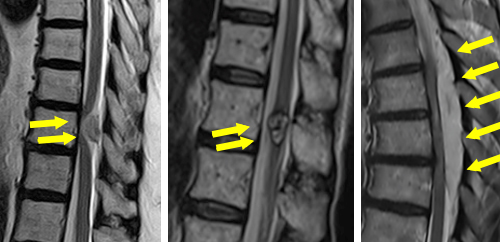

(左)術前のMRIでは、全体的に脊柱管内の狭窄があります。(中)片開き式脊柱管拡大術を施行し、金属性のプレートで椎弓を固定しています。(右)手術により脊柱管が拡大され、神経症状が改善しています。